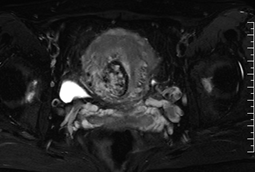

磁共振成像(MRI)能清晰显示子宫及其周围组织的解剖结构,有助于评估异常血管的走行、范围及其与邻近器官的关系,为临床诊断与治疗规划提供重要依据。

(子宫动静脉瘘MRI影像示意图)

典型MRI表现包括:

■ 子宫动静脉瘘MR-T1WI和T2WI序列子宫肌层或宫旁组织中可见卷曲扩张的流空信号,表现为无信号或低信号区域,类似血管的“流空效应”,提示存在异常扩张的血管团;

■ 增强T1WI序列病变部位可见迂曲的血管强化影,显示粗大的动脉血管与引流静脉直接交通,且无连接两者的毛细血管网;

■ 部分患者伴随子宫体积增大,子宫肌层交界区可能破坏,出现锯齿状或不规则的血流相关信号,提示病变累及肌层;

■ MRI可清晰显示动静脉瘘与周围组织(如宫旁血管、膀胱、直肠等)的关系,帮助评估病变范围及是否侵犯邻近器官。